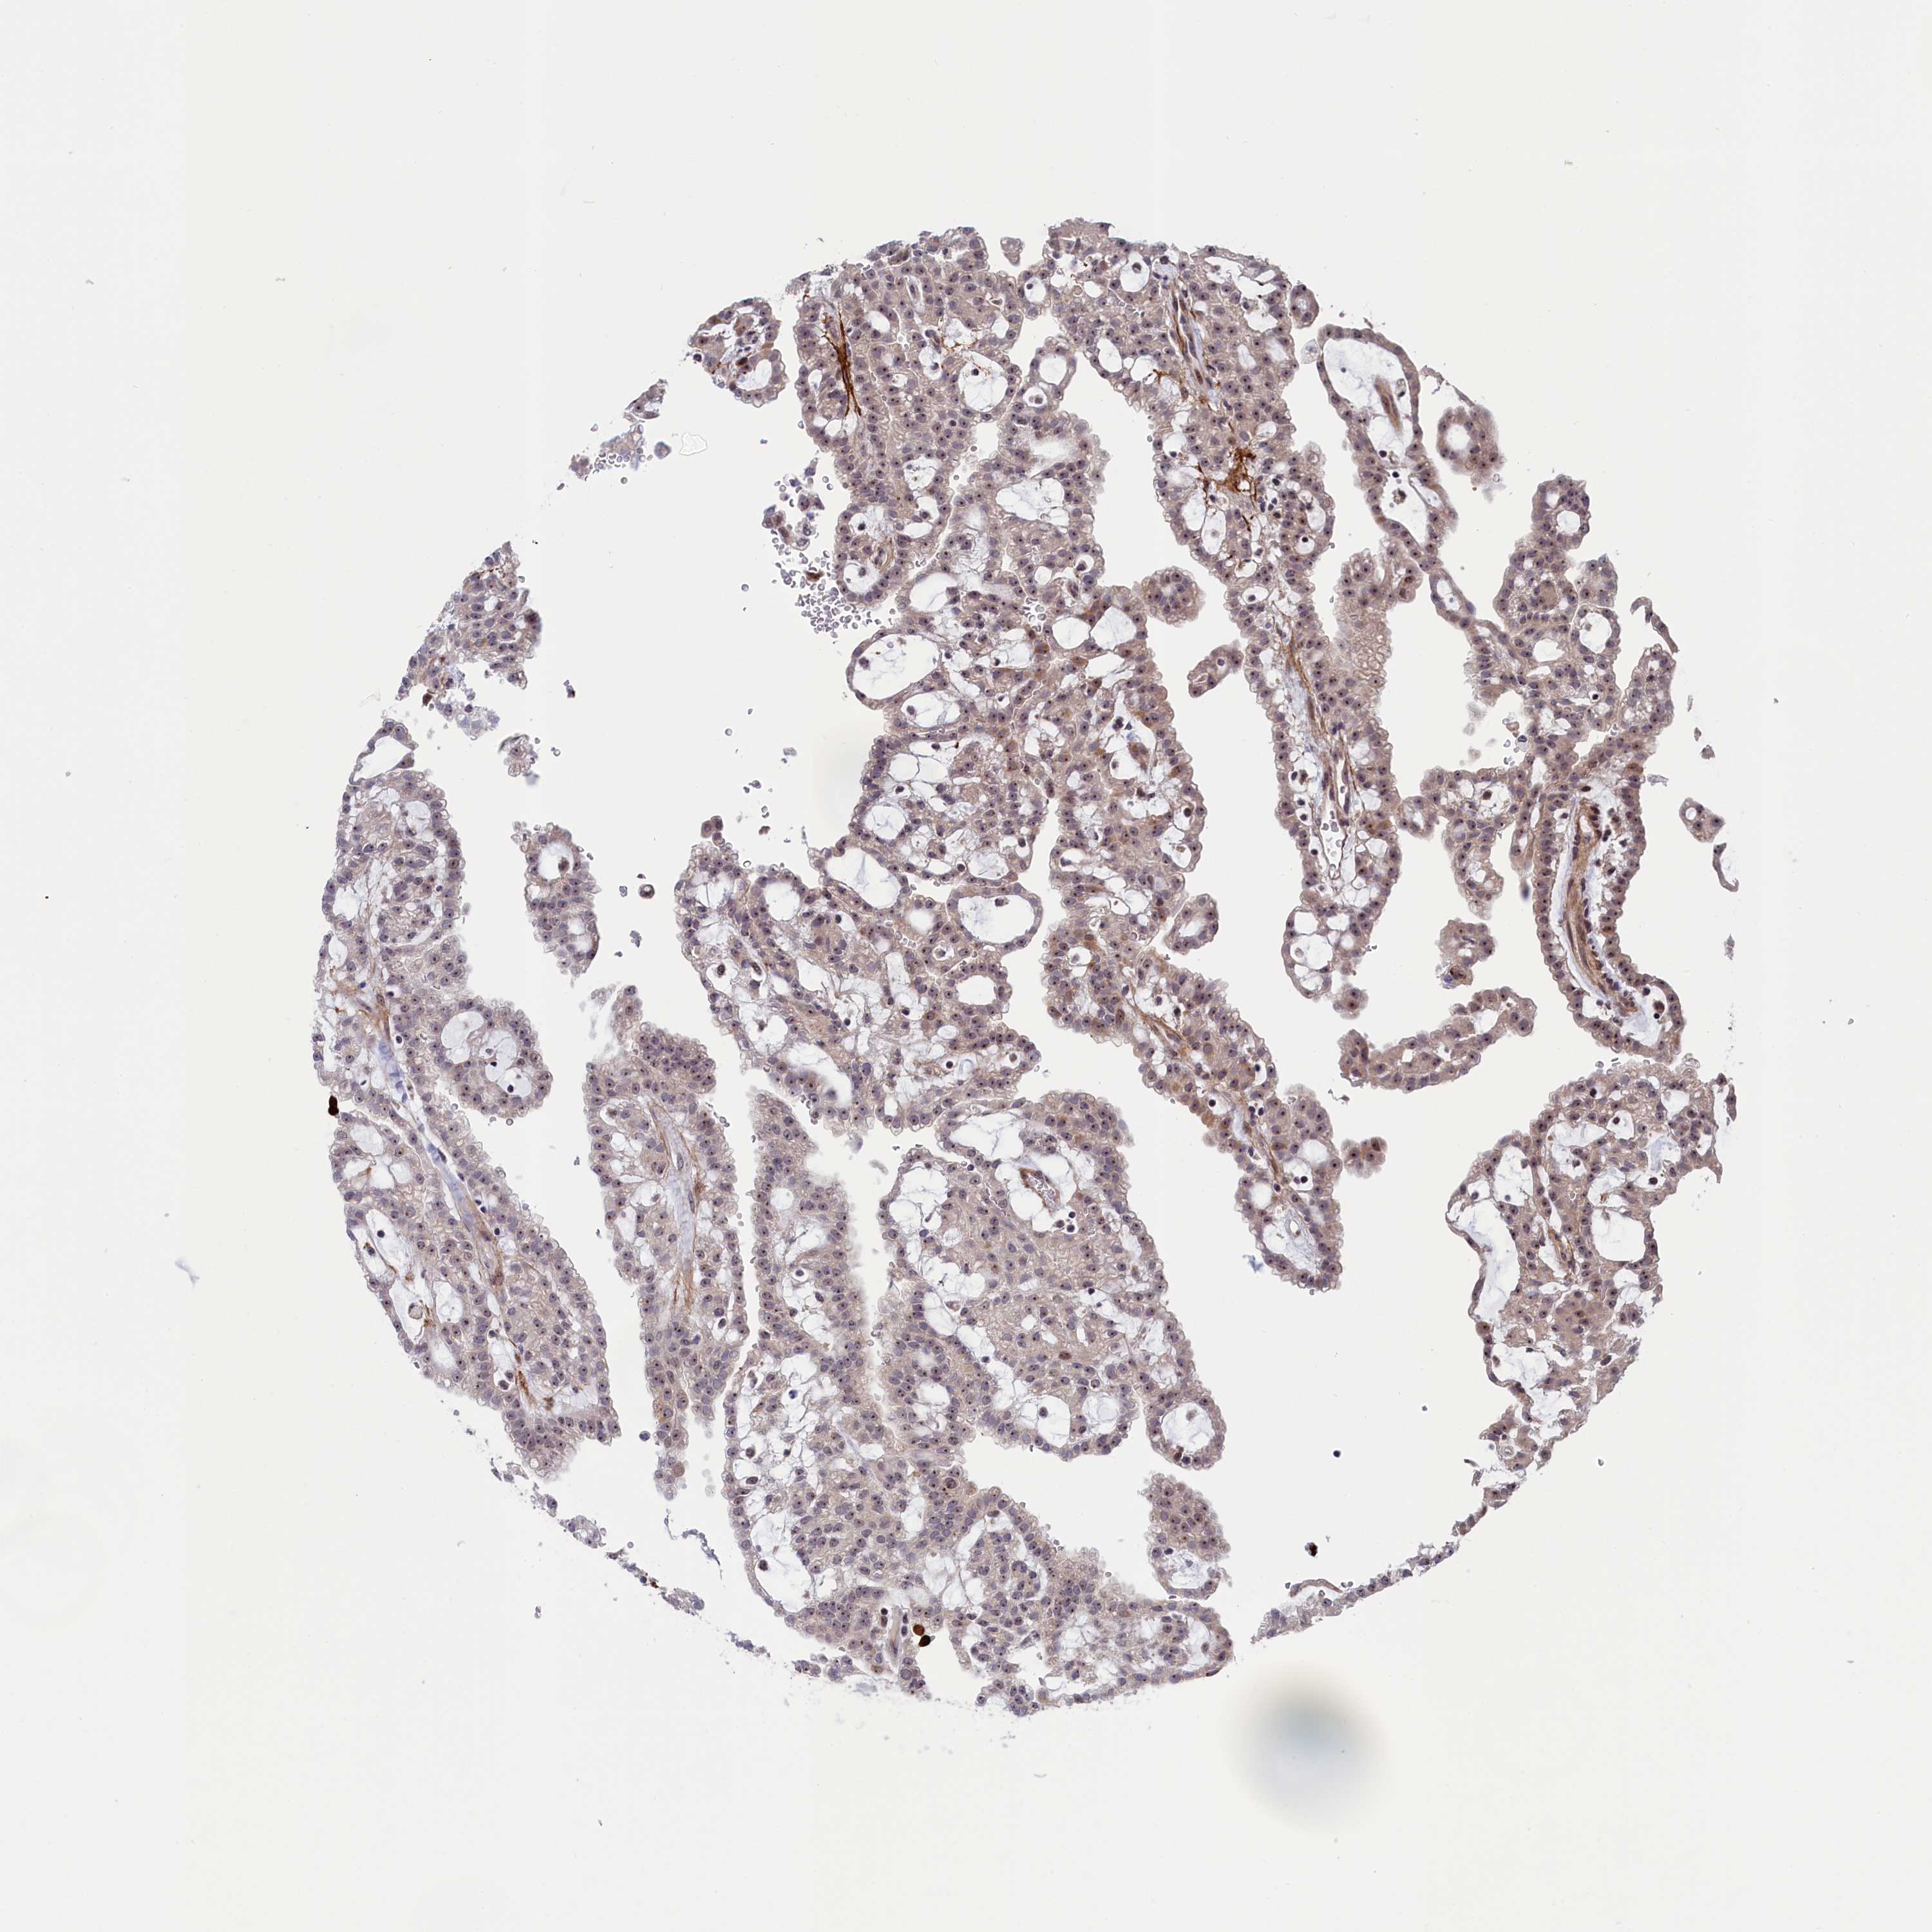

CANCER RENAL CANCER Show tissue menu

KICH TCGA KIRC TCGA KIRC VALIDATION KIRP TCGA PROTEIN RCC CPTAC PROTEIN EXPRESSION